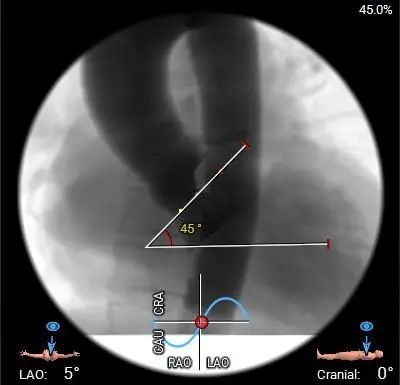

术前CT评估

主动脉根部测量

三叶式主动脉瓣,中重度钙化并增厚,水平夹角45°;LVOT敞口